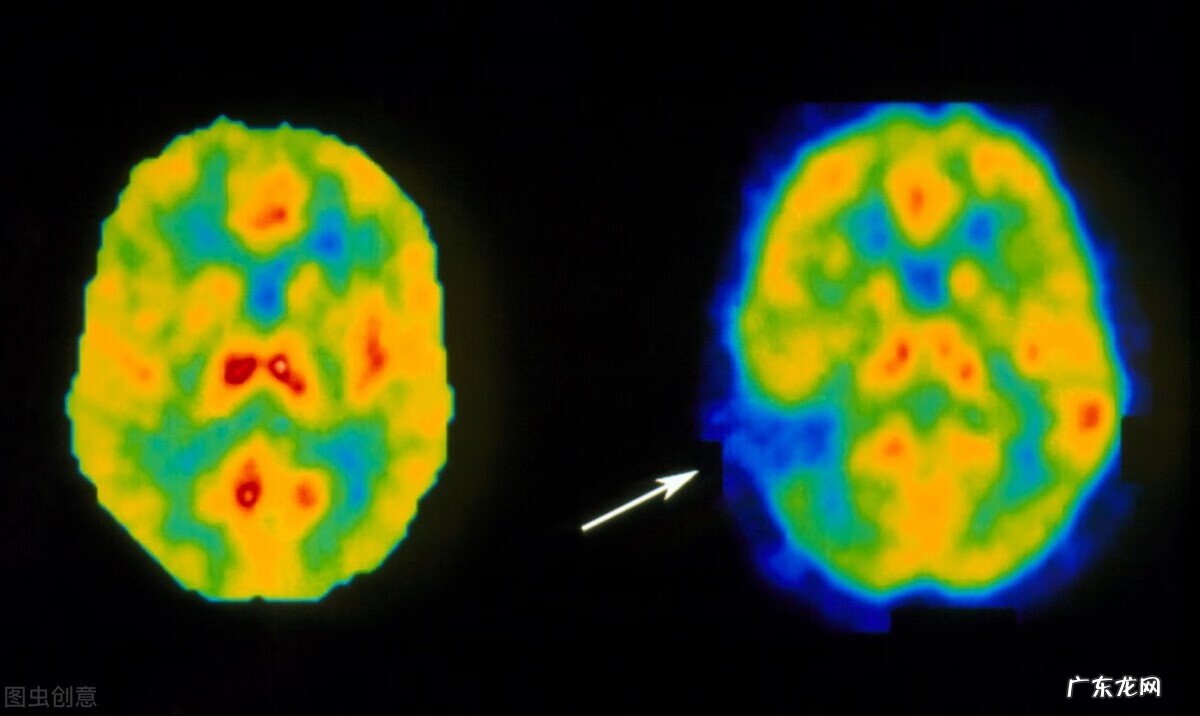

还有一部分人还有视力的障碍,看不见东西了,或者有一部分东西他看不见,当我看到你的时候,旁边的这些余光的东西他都看不见,我们叫偏盲 。

视觉中枢障碍

【脑中风是什么意思 何谓脑中风】当然还有很多病人出现眩晕、头痛等等系列的症状,这些都有可能是脑卒中的一些临床表现或者是常见的症状 。